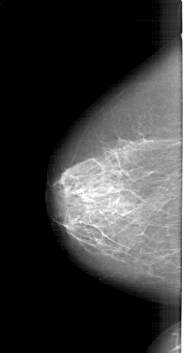

A_1390_1.LEFT_MLO

LEFT_CC LINES 5986 PIXELS_PER_LINE 3136 BITS_PER_PIXEL 12 RESOLUTION 43.5 NON_OVERLAY